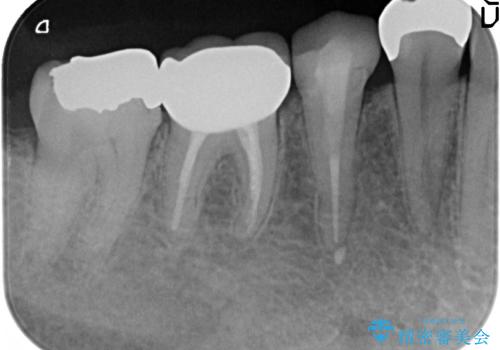

診査の結果右下6の歯の神経が死んでいたため、根管治療を行いました。

その後症状の消失を確認し、オールセラミッククラウンによる補綴を行いました。

今回用いたオールセラミッククラウンはジルコニアフレームという白い素材の上にセラミックを盛っているため、審美性が非常に高いのが特徴です。

また、ジルコニアは人工ダイヤモンドの材料にも使われているほど高い強度を持っており、そのためオールセラミッククラウンは審美性だけでなく、奥歯やブリッジの補綴も可能とするクラウンです。